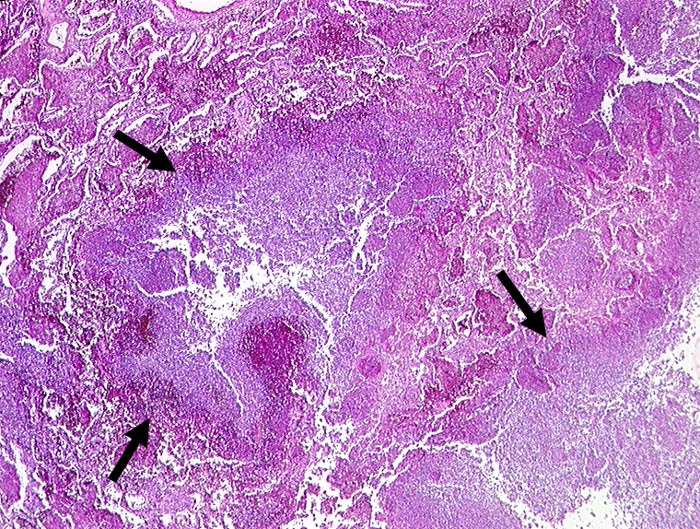

PathoPic ID 195 - abszedierende Pneumonie

abszedierende Pneumonie

Entzündung infektiös

Lunge

Im Zentrum und rechts unten im Bild zerstörtes Lungenparenchym. Anstelle des Parenchyms

►

eitrige Einschmelzung.